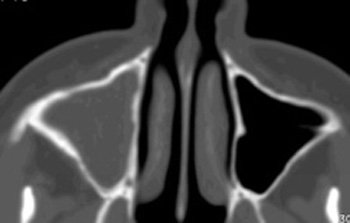

Con sospecha de sinusitis maxilar derecha crónica de probable origen odontógeno, se solicita una tomografía computarizada (TC) de senos paranasales, observándose una ocupación del seno maxilar y etmoides anterior derecho, en probable relación con quiste periapical de pieza 1.6 y posible disrupción focal del suelo del seno (ver Imágenes nº 1-3 al final del texto).

Imagen nº1: TC corte coronal.

Imágenes 2 y 3: TC cortes axiales.